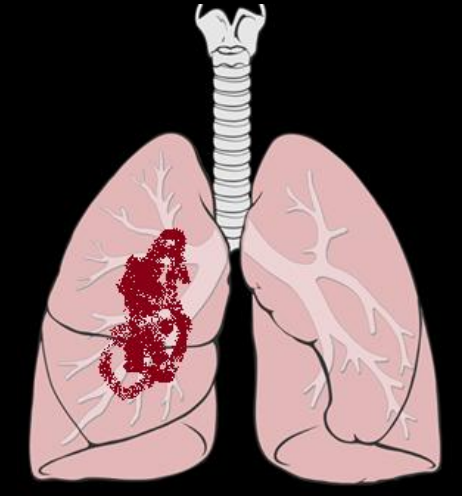

Q

¿Qué distribución tiene la lx?

A

Central o parahiliar unilateral

Periférica o subpleural unilateral